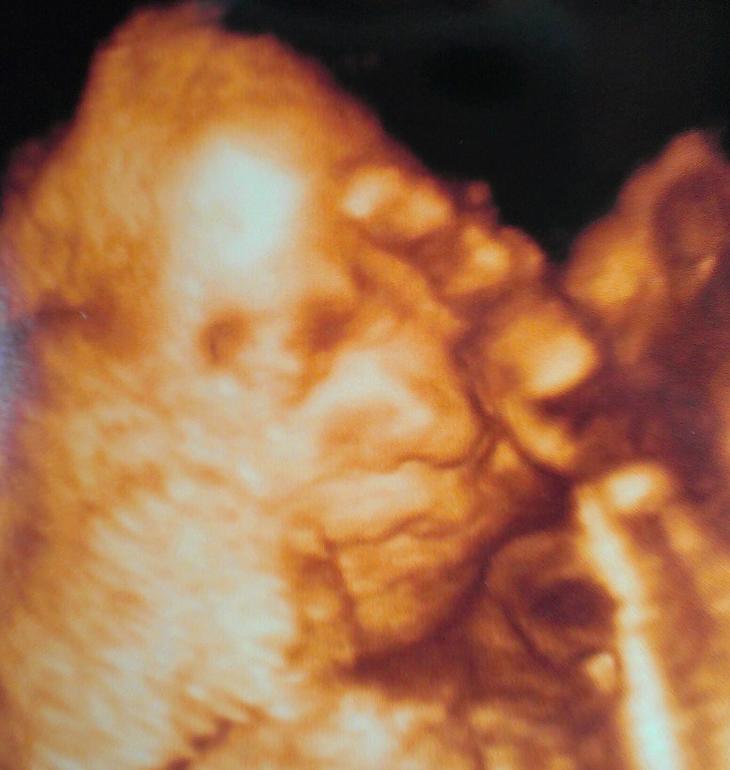

Срок по узи на 2 дня больше, чем по М. Предв.вес 880 гр. Большой мальчик, уже 25,6 нед. :) Пришли на узи, а наш мальчик спит, уткнувшись носом в плаценту, фото личика не сделать. Пришлось тормошить его минут 10, потом подвинулся, пару раз пнул, позевал и снова уснул )))) Но фото сделали к счастью. Похож на папу на этих фото. Фото под катом.